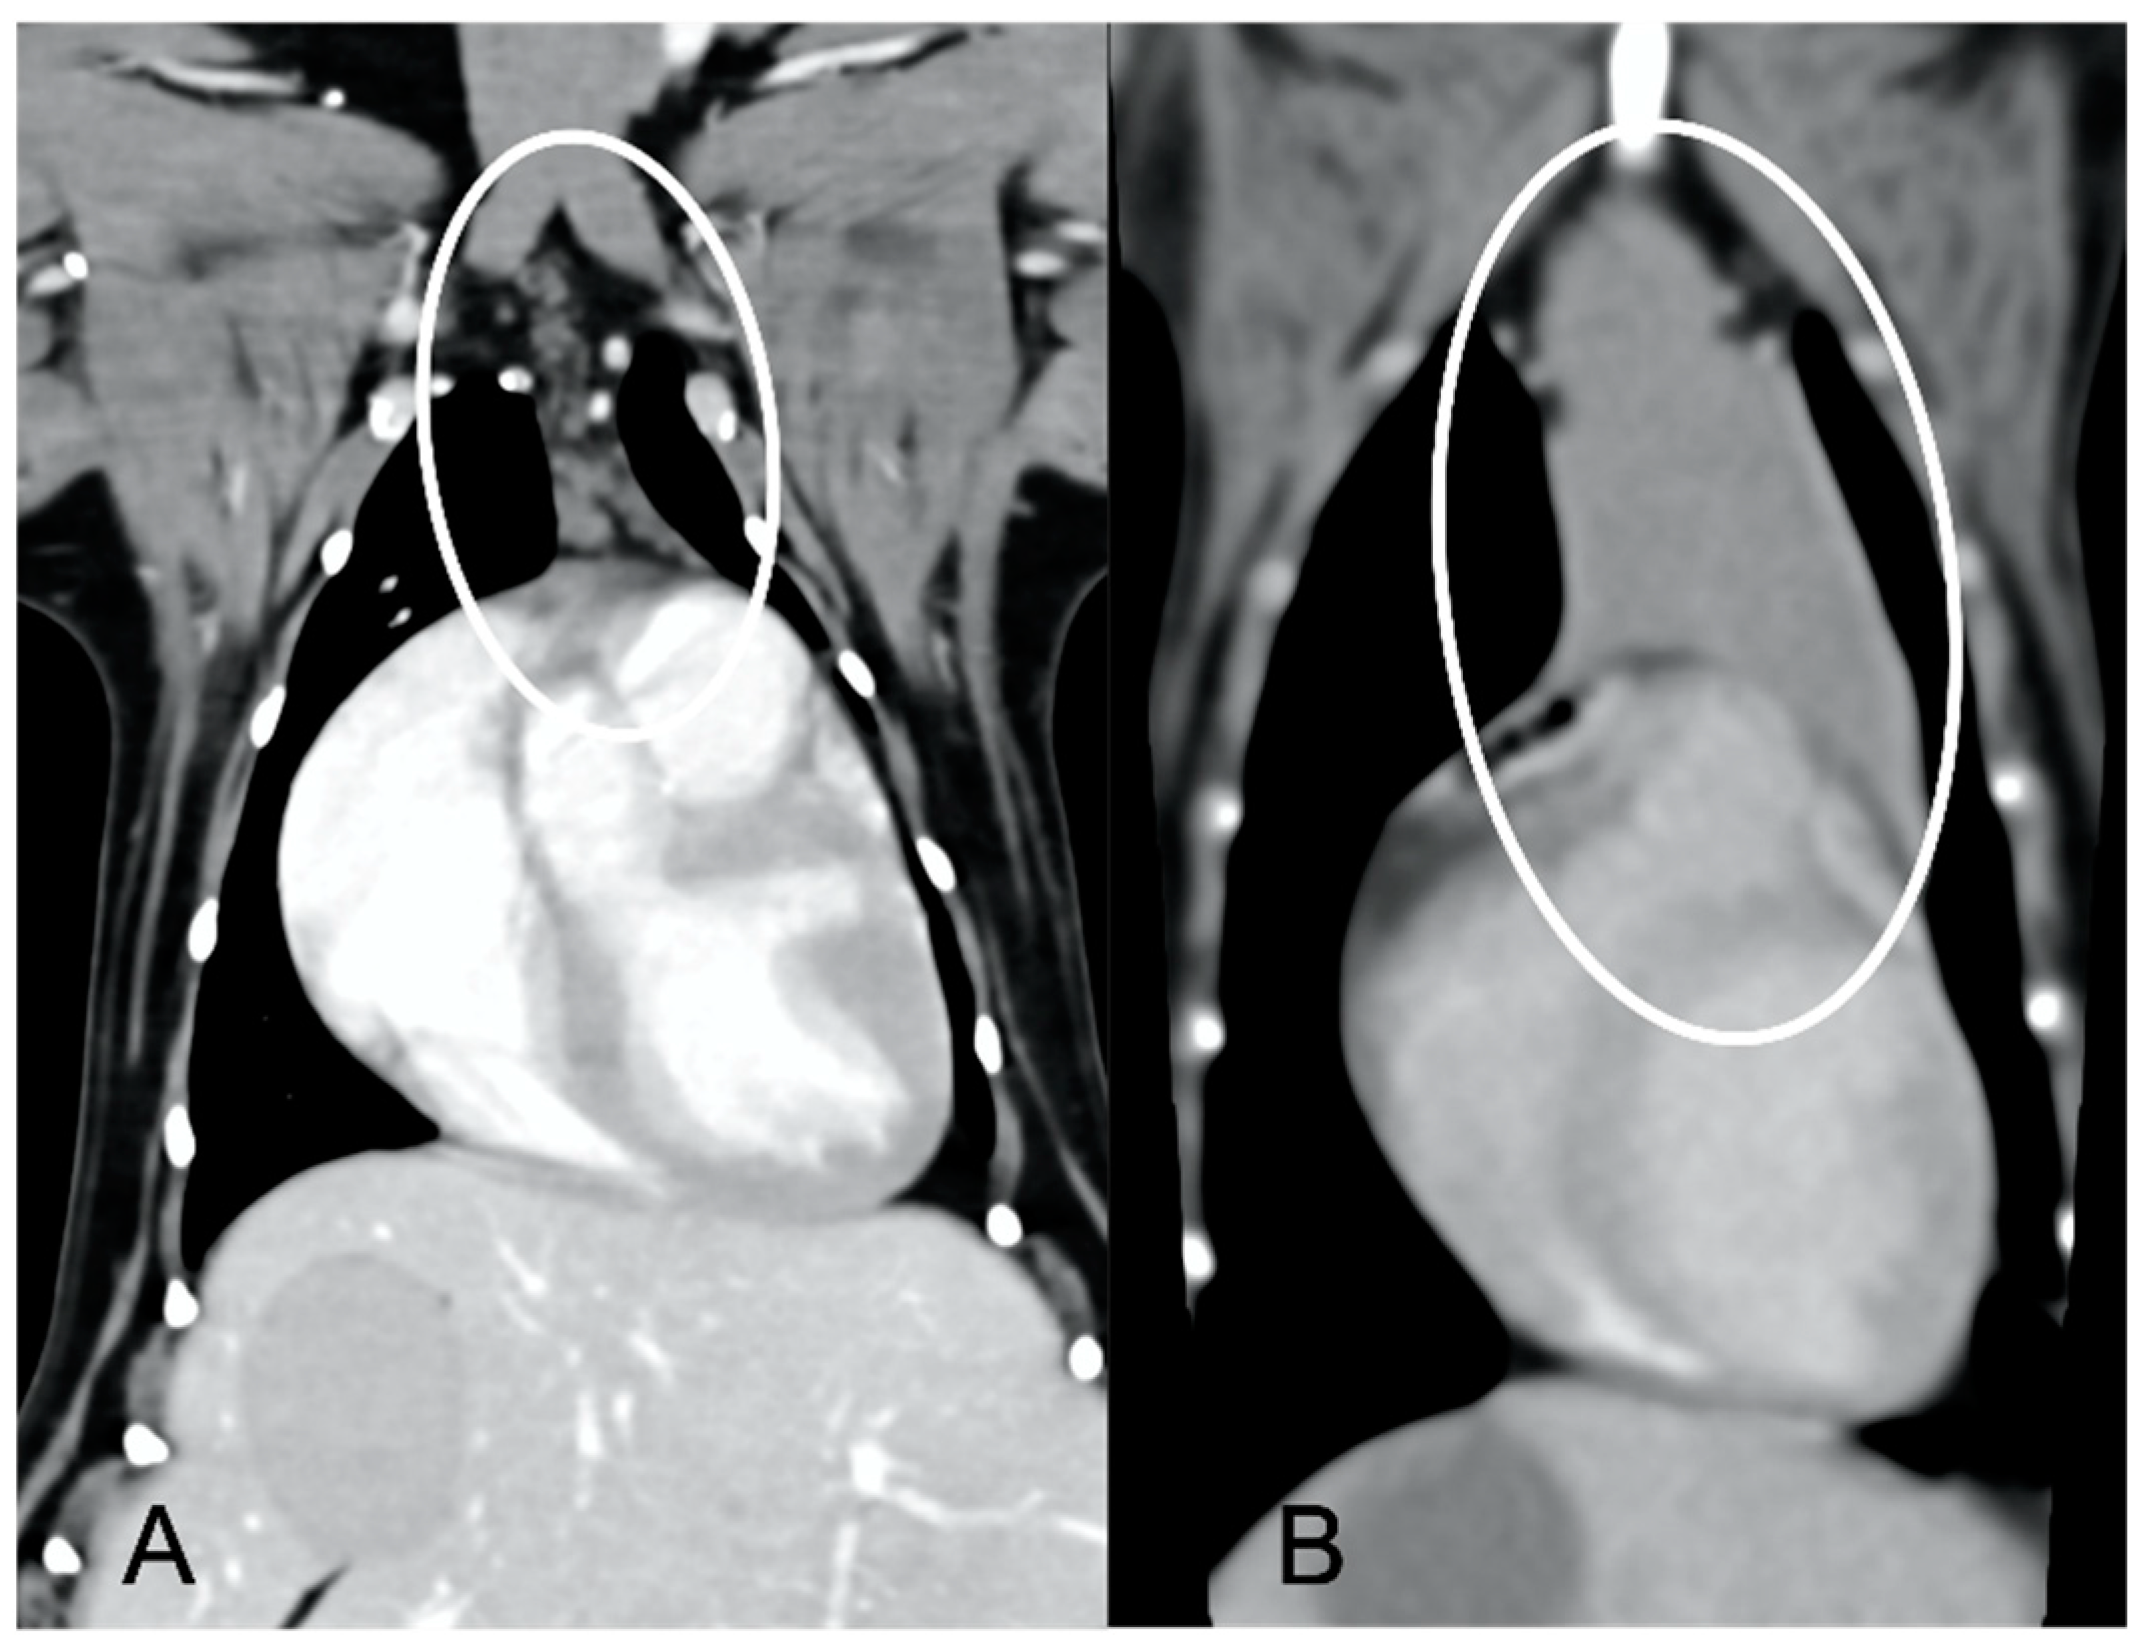

In both groups, most of the dogs presented with a triangular thymus (Figure 1); in the adult group, some dogs had an elongated thymus, and in the juvenile group, some dogs had a flattened thymus (Figure 2).

The overall appearance was lobulated in all of the adult dogs and homogeneous in all of the juvenile dogs (Figure 1 and Figure 3). The thymus was left-sided in all of the adult dogs, while it was located in the midline in a few juvenile dogs; one presented a thymus on the right side due to situs inversus (Figure 4). The maximum dimension of the thymus in the adult dogs group was always the length, while in some juvenile dogs, the maximum diameter was the width (Figure 2). The dimensions of the thymus were variable between different patients, with several breeds included and large differences in body weight between the dogs. For this reason, a ratio between the maximum diameter of the thymus (measured in cm) and the body weight (measured in kg) was calculated for each dog. The median ratio in the adult dogs group was 0.2 (minimum: 0.06; maximum: 0.4), while in juvenile dogs, it was 0.4 (minimum: 0.1; maximum: 1.4). The dogs with the higher ratio (>1) were in the juvenile group and they presented with spinal a cyst and enteritis and were 6 and 7 months old, respectively. The dogs with the lower ratio (<0.1) were in the adult group and they presented with muscular hemangiosarcoma (one dog) and synovial cell sarcoma (two dogs) and were 2, 6, and 8 years old, respectively.

Figure 2. Example of a flattened thymus (circled) in a young dog. Post-contrast dorsal CT reconstruction (A) and transverse image (B) of the same patient. Note the flattened appearance of the thymus, enlarged in the laterolateral direction (width) and smaller in the dorsoventral direction (thickness).